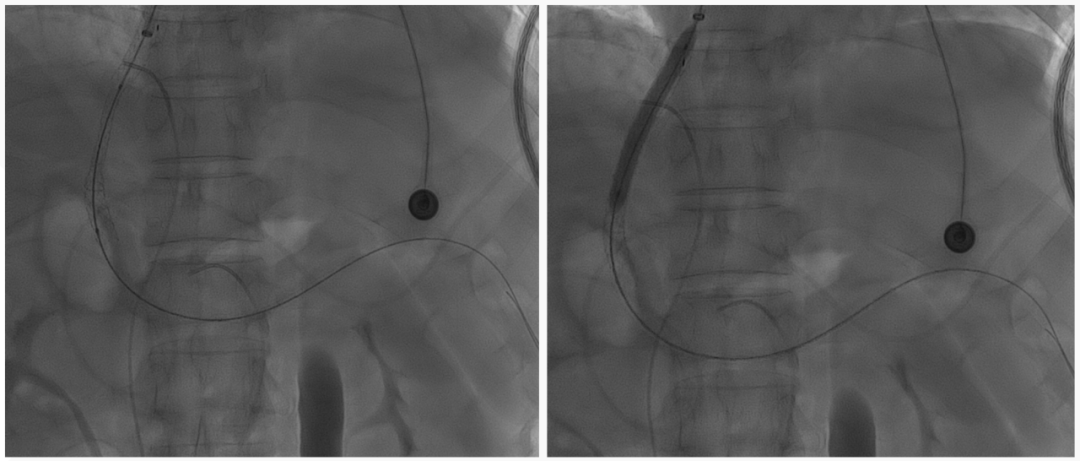

至肠系膜上动脉行间接门静脉造影,未见门静脉显影,可见巨大异常分流道,遂至脾动脉行间接门脉造影可见门静脉异常纤细,肠系膜下静脉见异常分流道形成

以微导管行肝动脉标记辅助穿刺,门静脉造影显示血流呈离肝状态

超选至肠系膜下静脉异常分流道,予以栓塞18mm的Amplatzer vascular plug及适量25%生物胶,造影示异常分流道消失

8mm覆膜支架释放于肝内穿刺道,考虑门脉纤细,遂以6mm球囊后扩张

异常分流道栓塞后,再次行门静脉造影,血流呈向肝状态,食管胃底曲张静脉较前更显著,微导管超选至曲张的胃冠状静脉,予以弹簧圈及25%生物胶栓塞,造影示曲张静脉消失,肝内门脉显影较术前显著改善